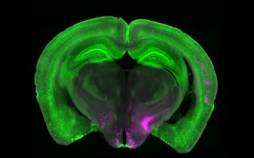

دانشمندان آلمانی راهی برای فعالسازی مجدد سیستم پاکسازی مغز پیدا کردند؛ فرآیندی که با اصلاح برچسبگذاری پروتئینها، میتواند زوال عقل را در سنین بالا

[ادامه]

محققان در یک بررسی جدید دریافتند، آموزش مهارتهای گوناگون به سالمندان به جوان ماندن مغز آنها کمک میکند.

یافته محققان فنلاندی؛ مطالعات نشان می دهد زایمان زودهنگام موجب تغییر قابل توجه در عملکرد مغز نوزاد در طول زمان خواب می شود و می تواند بر سایر عملکردها هم تاثیر منفی داشته